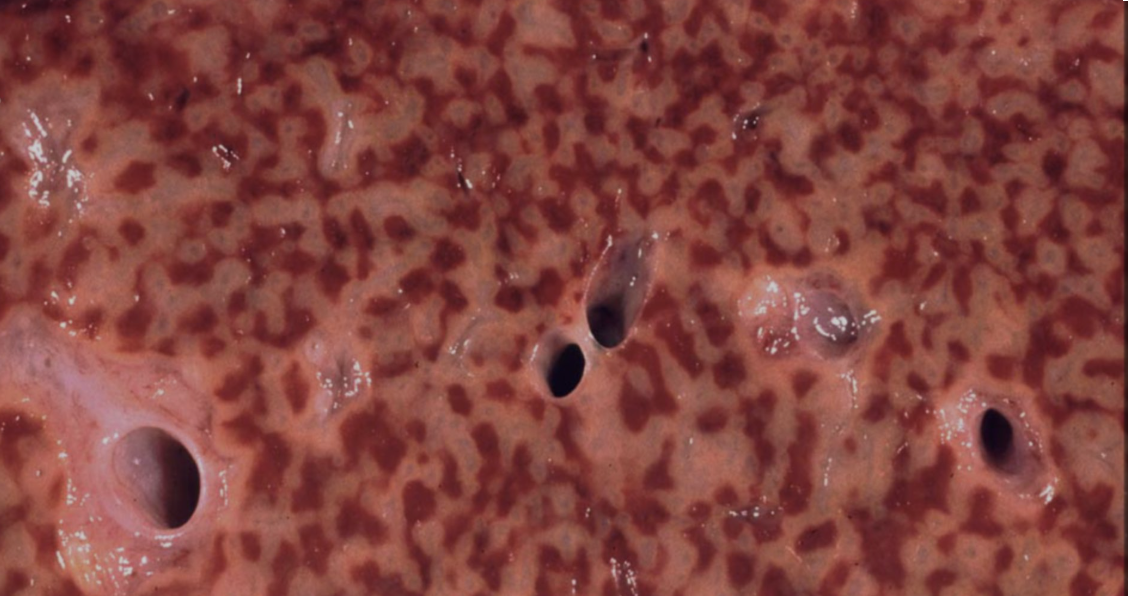

What type of cells are these?

These macrophages are sometimes called “heart failure cells” because of their association with pulmonary congestion with congestive heart failure. Pulmonary congestion with dilated capillaries and leakage of blood into alveolar spaces leads to an increase in hemosiderin-laden macrophages. The brown granules of hemosiderin from breakdown of RBCs.

Hemosiderin laden macrophages are also seen in diffuse alveolar hemorrhage syndromes such as granulomatosis with polyangiitis, anti-GBM disease, and other systemic vasculitides.